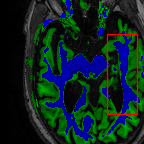

Sparsity LI 2D CNN 3D CNN Ours GT

4 Refer to caption (a) 0.6787/0.7972 Refer to caption (b) 0.8143/0.8776 Refer to caption (c) 0.8190/0.8714 Refer to caption (d) 0.8664/0.9085 Refer to caption (e) GM/WM

Refer to caption (f) 0.6808/0.7161 Refer to caption (g) 0.8103/0.8631 Refer to caption (h) 0.7950/0.8606 Refer to caption (i) 0.8598/0.9115 Refer to caption (j) GM/WM

8 Refer to caption (k) 0.5139/0.7240 Refer to caption (l) 0.6619/0.8224 Refer to caption (m) 0.6878/0.8584 Refer to caption (n) 0.7798/0.8853 Refer to caption (o) GM/WM

Refer to caption (p) 0.5910/0.6947 Refer to caption (q) 0.6516/0.8021 Refer to caption (r) 0.6507/0.8186 Refer to caption (s) 0.7471/0.8540 Refer to caption (t) GM/WM

Figure 6: Visual comparison of gray matter (Green)/white matter (Blue) segmentation over different methods, with respective DICE scores listed under the images.

In Fig. 6, we demonstrate the advantage of the proposed method in brain matter segmentation. It is clear that although 2D and 3D CNN generates visually plausible interpolation as presented in Fig. 5, the brain matters are easily misclassified due to incorrect anatomical structures and blurred details.